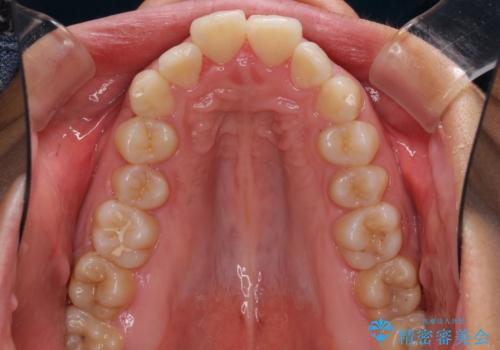

- 上下の出っ歯を気にして来院された患者様です。

口元を積極的に引っ込めるために、上下左右の第一小臼歯を4本抜歯することとしました。

しっかりと通院するようになってからは順調に治療が進み、横顔の印象が変わるほどスッキリとした口元となりました。